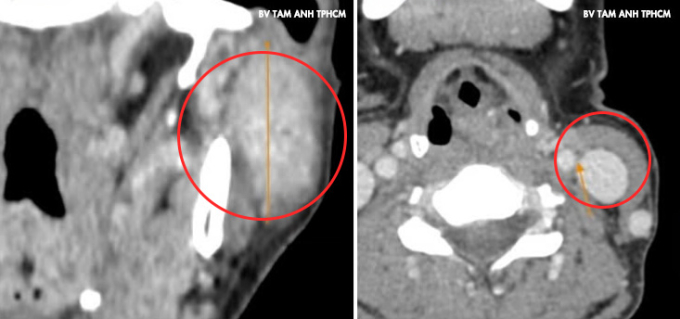

U xuất hiện ở góc hàm mang tai trái của chị Dương một năm trước, nhỏ và không đau, không liệt mặt, khác với đặc điểm chung của loại u này là thường phát triển rất nhanh gây đau và liệt dây thần kinh mặt. Gần đây, u sưng hơn khiến mặt mất cân đối, chị đến Phòng khám Đa khoa Tâm Anh Quận 7 kiểm tra. Kết quả chụp CT và siêu âm ghi nhận khối u dài hơn 4 cm chiếm gần hết mô tuyến mang tai trái, phát triển vào trong xâm lấn dây thần kinh 7 và tĩnh mạch sau hàm. Cạnh trước khối u có hạch gần 1 cm và hai hạch hơn 1 cm vùng cổ. Kết quả sinh thiết chọc hút tế bào kim nhỏ là u tuyến mang tai hóa bọc, chưa xác định ung thư.

Ảnh chụp CT ghi nhận khối u lớn vùng mang tai trái của chị Dương. Ảnh: Bệnh viện Đa khoa Tâm Anh